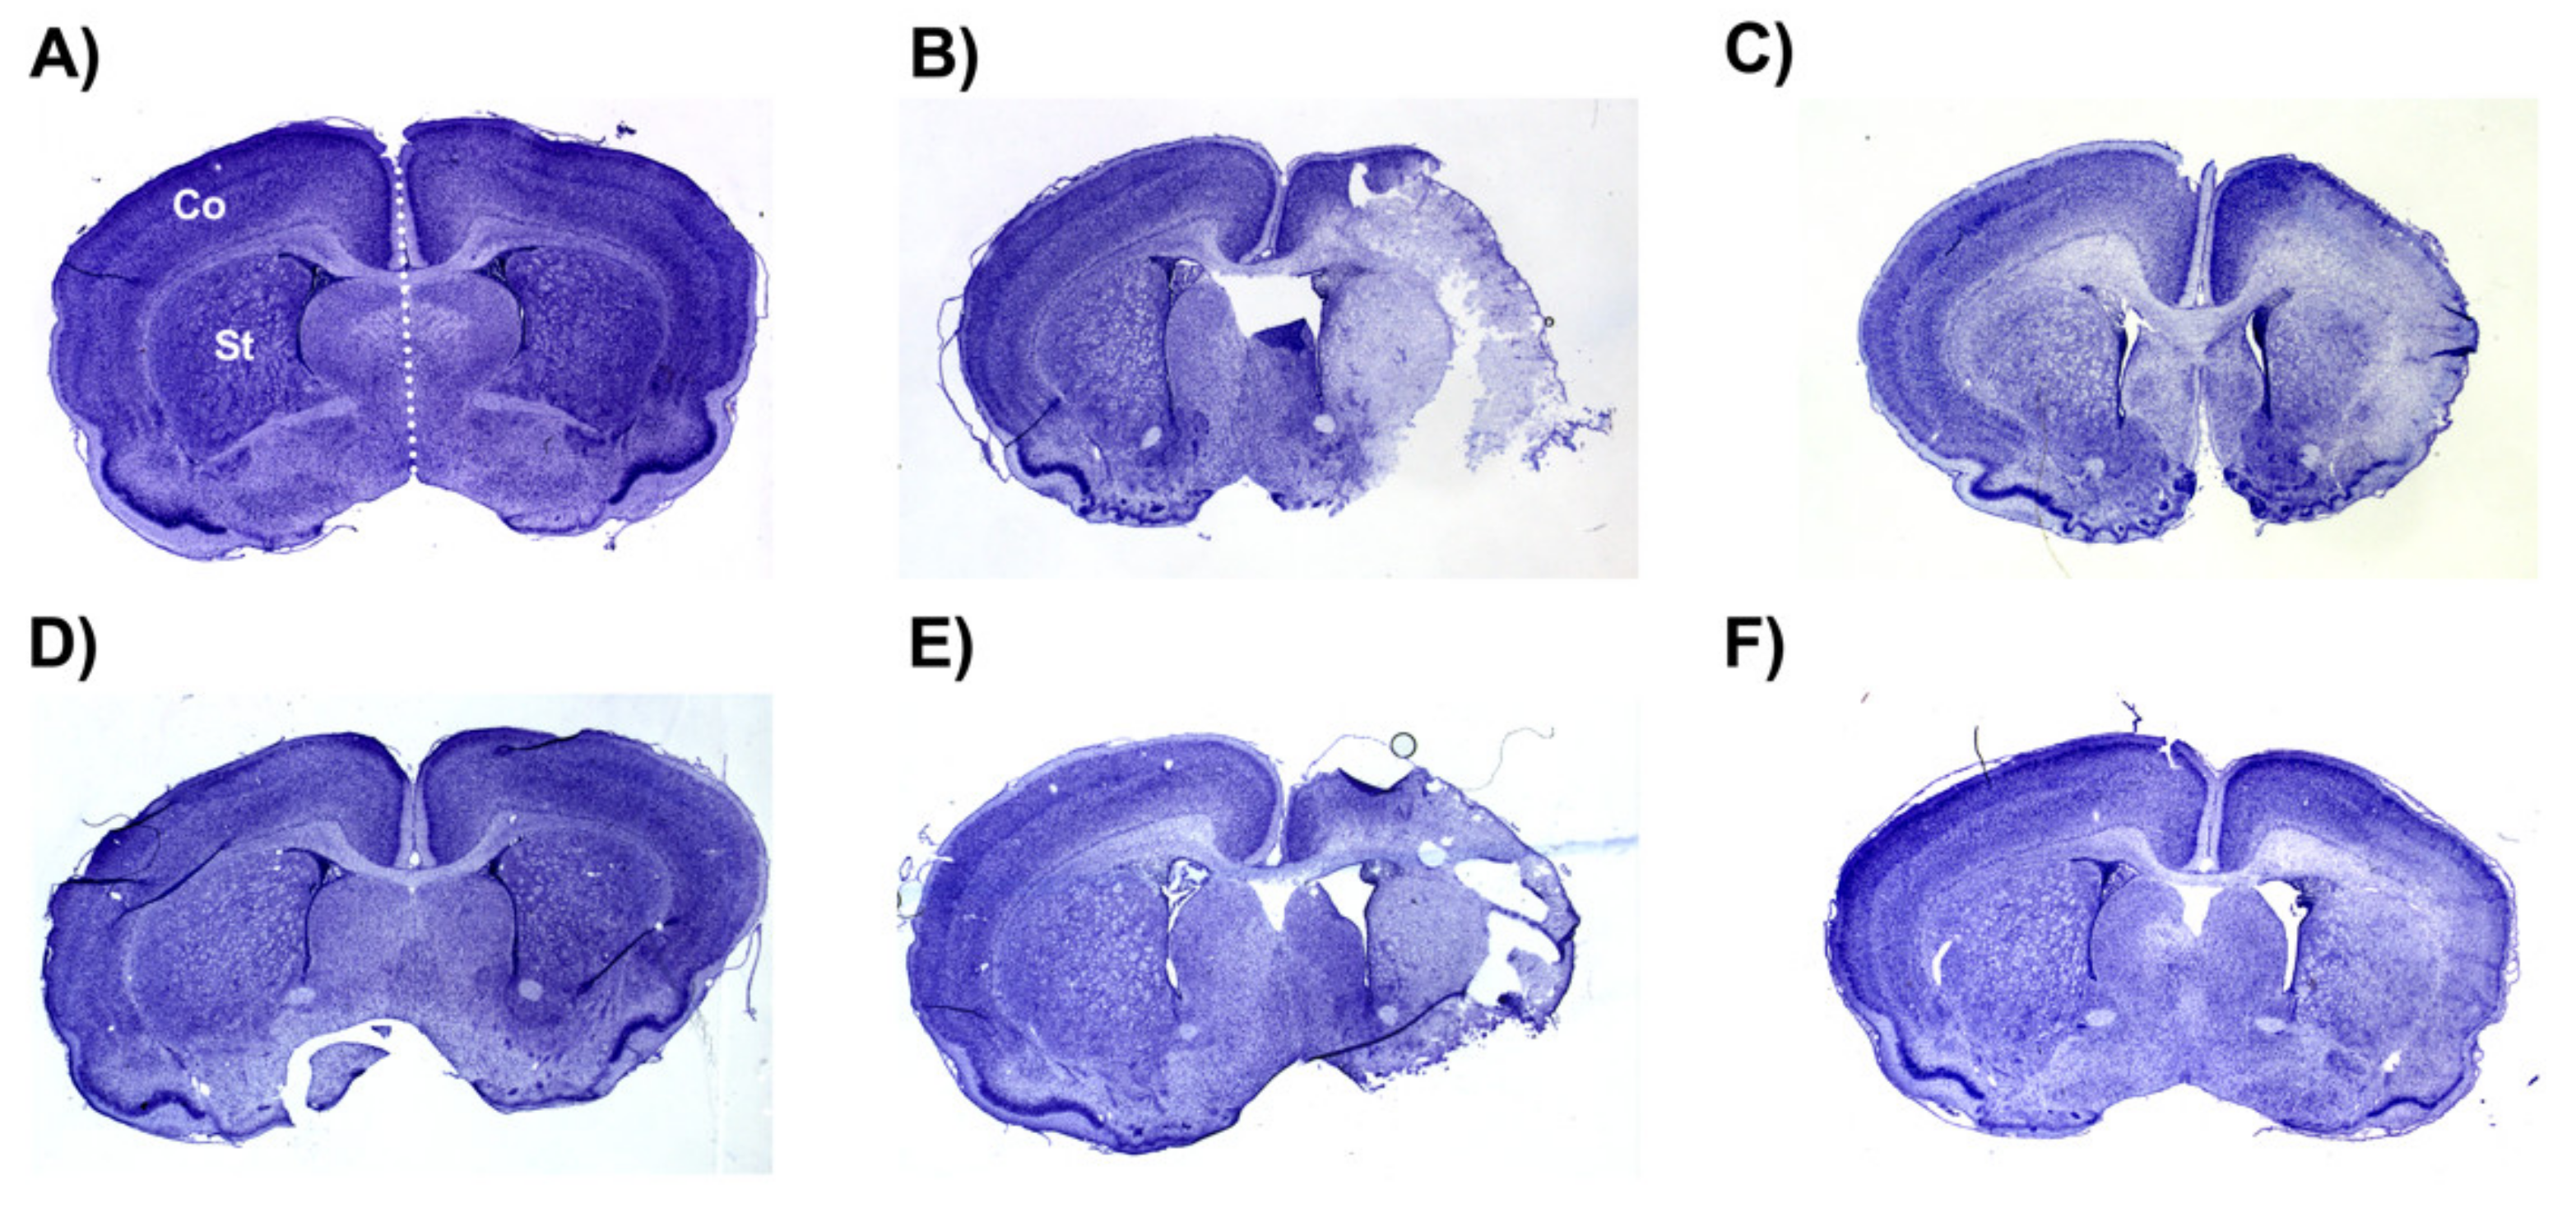

Figure 7.

Representative images of infarct volumes in the neonatal rat brain 72 h after exposure to hypoxia–ischemia (HI). Coronal cross-sections of the brain stained with cresyl violet for female sham placebo (A), female HI placebo (B), female HI 30 mg/kg IAIP-treated (C), male sham placebo (D), male HI placebo (E), male HI 30 mg/kg IAIP-treated (F) groups. The area for cerebral cortex (Co) and striatum (St) measurements is highlighted in (A). Hemisphere measurements were taken to the left or right of the midline (white dotted line), as highlighted in (A). Figure 5 and Figure 6 show the quantification of infarct volumes for all animals of each treatment group.

2.4. Brain Infarct Volumes

The average whole hemisphere infarct volumes in the HI-PL group were 71% in the males and 65% in the females, the average cortical infarct volumes were 80% in the males and 77% in the females and the average striatal infarct volumes were 91% in the males and 79% in the females (Figure 5 and Figure 6). These quantities of infarct volumes suggest a severe degree of brain injury for the Rice–Vannucci model. Representative images of infarct volumes in the placebo-treated males and females are shown in Figure 7. There were no significant differences in the extent of the infarct volumes in the HI-PL group compared with the HI 30, HI 60, or HI 90 mg/kg hIAIP-treated groups in the whole hemisphere or cortex in the males (Figure 5A,B), or any of the brain regions in the female neonatal rats (Figure 6). There were significantly lower infarct volumes in the striatum of the HI 30 (0.74-fold, p < 0.05), HI 60 (0.74-fold, p < 0.05) and HI 90 (0.74-fold, p < 0.05) mg/kg hIAIP-treated groups compared with the HI-PL-treated group of males (Figure 5C). Significant differences were not observed between the infarct volumes of HI 30, HI 60, or HI 90 mg/kg hIAIP-treated groups for either sex in any brain region. Therefore, all animals in the HI 30, HI 60, and HI 90 mg/kg hIAIP-treated groups were combined into one hIAIP group per sex for subsequent analysis (Figure 8 and Figure 9). The combined HI-hIAIP (30, 60, 90 mg/kg) group of males exhibited significantly lower infarct volumes than the HI-PL group in the hemisphere (0.75-fold, p < 0.05), cortex (0.77-fold, p < 0.05) and striatum (0.74-fold, p < 0.05; Figure 8B). Significant differences were not observed in the females (Figure 8A).

4.6. Histology

Every seventh cryosection per 2 mm brain segment was selected for histological quantification. The number seven was randomly decided. The slides were removed from the −80 °C freezer and air-dried overnight. Slides were then exposed to 1:1 chloroform and absolute ethanol (20 min). Sections were each stained with cresyl violet (0.1% w/v, 6 min; MilliporeSigma, St. Louis, MO, USA), then rinsed with dH2O (1 min). The sections were then subjected to 4 min washes of 95% ethanol, 100% ethanol, and 95% ethanol. The slides were then air-dried overnight and mounted (Cytoseal XYL, Richard-Allan Scientific, Canton, MI, USA). Images of each section were obtained using a Micropublisher 6 CCD Camera (QImaging, Surrey, BC, Canada). Stained tissue volume was measured with ImageJ by two independent observers that were not aware of the group assignments. Total stained tissue, stained cortex, and stained striatum were quantified for the left and right hemispheres of each brain section (Figure 7). Stained tissue volumes were calculated using the known 2 mm distances between each section. Total infarct volume was examined using the following formula: infarct (%) = [1 − (ipsilateral volume/contralateral volume)] ×100 [18,51]. Negative values were adjusted to 0 to signify no infarct.